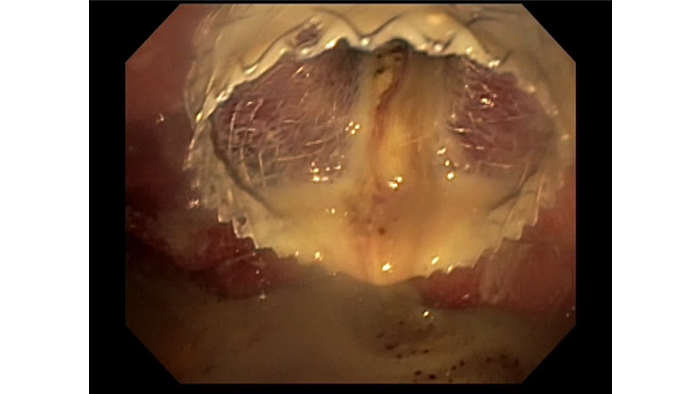

EUS with Doppler revealed a large wall of necrosis measuring 20cm. The lesion had a thick wall and contained solid debris with copious amounts of liquid, common for WON with liquefaction.​

Using the AXIOS Stent, the WON was accessed via a transgastric route. A 20mm wide and 10mm long AXIOS™ LAMS was deployed across the gastric wall.​